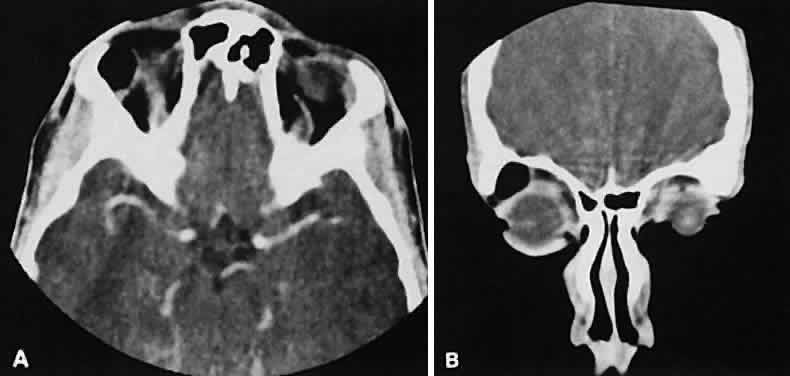

Graves' orbitopathy probably represents the most frequent cause of proptosis and EOM enlargement. The CT findings are fairly stereotyped and typically display various degrees of EOM enlargement (Fig. 7). The inferior rectus muscle usually is affected earliest, followed by the medial rectus, superior rectus, and finally the lateral rectus muscle. Rootman and colleagues13 noted more frequent involvement of the superior rectus/levator and medial rectus muscles than what had been reported previously with Graves' orbitopathy. These muscles can be affected in isolation, with the exception of the lateral rectus. To the best of our knowledge, isolated lateral rectus enlargement has not been reported in Graves' orbitopathy and in our experience usually is associated with a sphenoid wing meningioma.

Fig. 7. Graves' orbitopathy with two variations. Axial (A) and coronal (B) views show symmetric fusiform enlargement of the extraocular muscles with tapered muscle insertions. Note the predominant enlargement of the inferior, medial, and superior rectus muscles with lesser involvement of the lateral rectus muscle, a frequent pattern of enlargement in Graves' orbitopathy. Axial (C) and coronal (D) views of Graves' orbitopathy with expansion of retrobulbar ground substance and relative sparing of the extraocular muscles.

CT evidence of Graves' orbitopathy tends to be bilateral. Approximately 86% of patients with unilateral clinical findings have bilateral CT findings in our experience, which is consistent with the experience of others.42

Morphologically, the EOM belly is enlarged, with a gradual tapering toward and sparing of the tendinous portion of the muscle. Tendon involvement is a typical feature of orbital myositis. Tendon involvement helps to differentiate this lesion from Graves' orbitopathy, although Rootman and Nugent43 have noted a rare patient with Graves' orbitopathy with this finding.